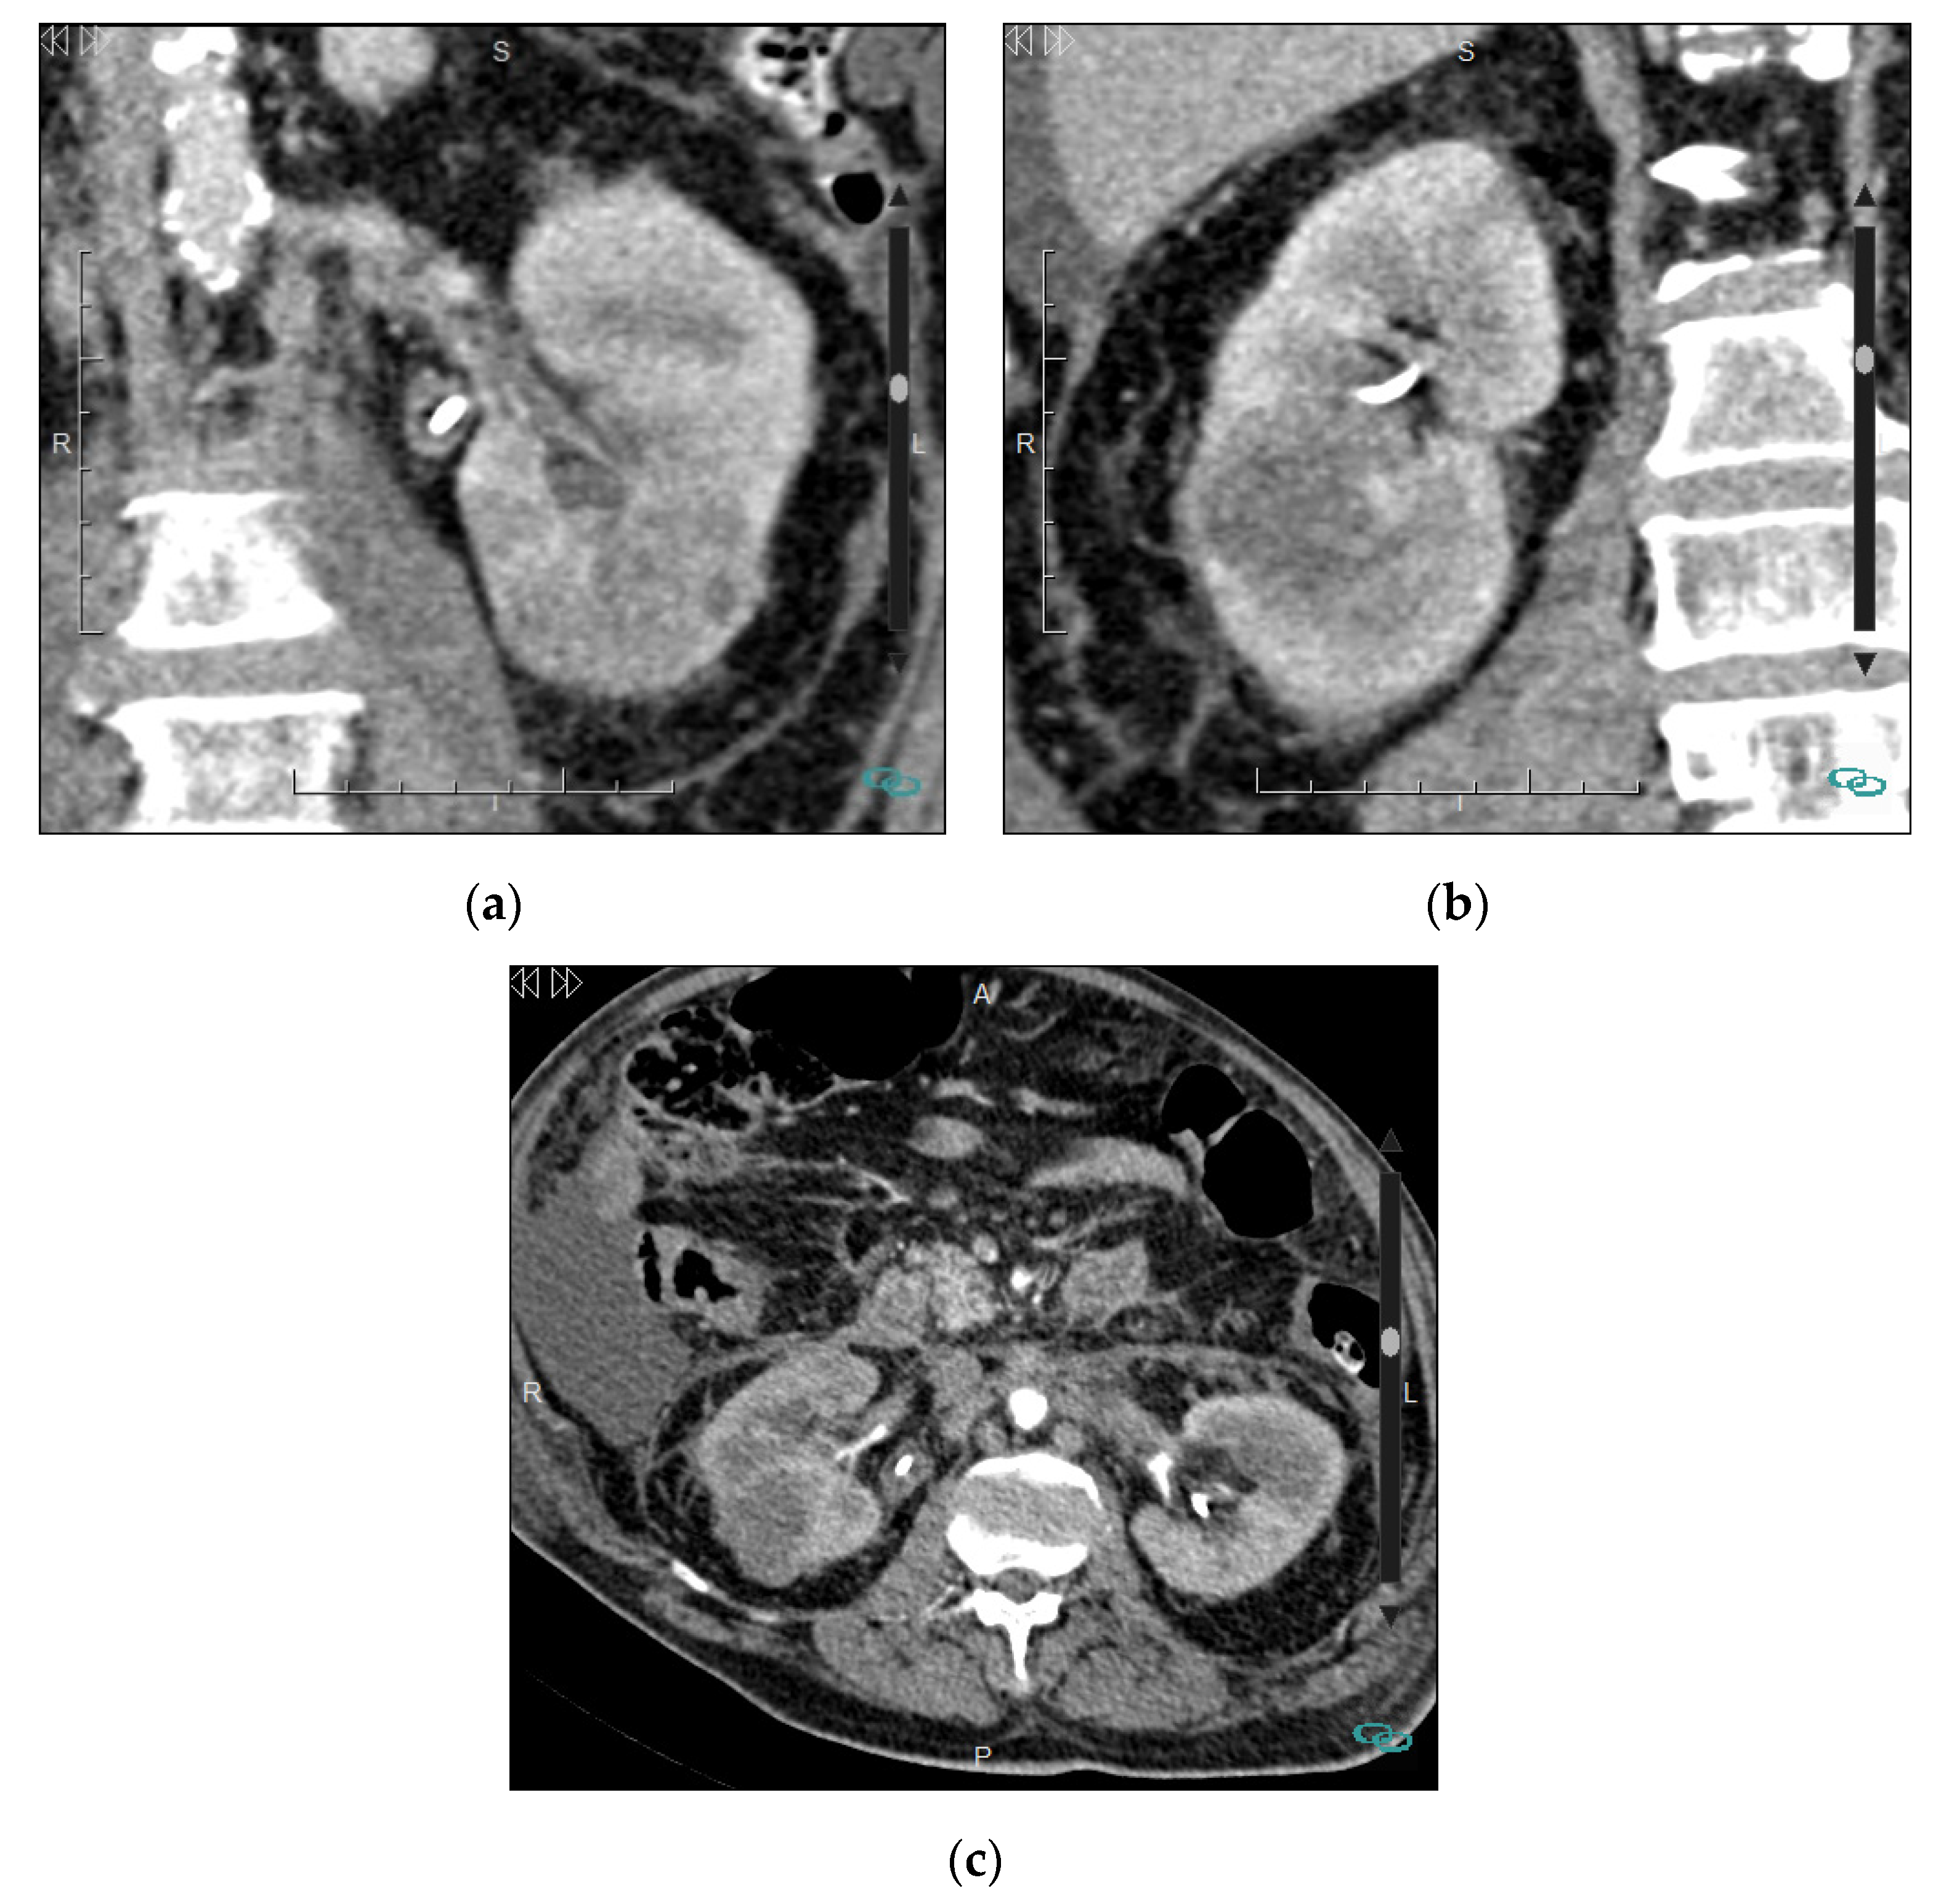

4.2. Infiltrative Masses

| Renal cell carcinoma | Clear cell, papillary, or chromophobe Renal medullary carcinoma Collecting duct carcinoma Sarcomatoid differentiation |

| Urothelial carcinoma | Transitional cell carcinoma Squamous cell carcinoma |

| Lymphoproliferative disease | Renal lymphoma Renal leukemia Extramedullary plasmacytoma |

| Metastases | |

| Inflammatory conditions and pseudotumors | Developmental renal pseudotumors Pyelonephritis/abscess Xanthogranulomatous pyelonephritis |